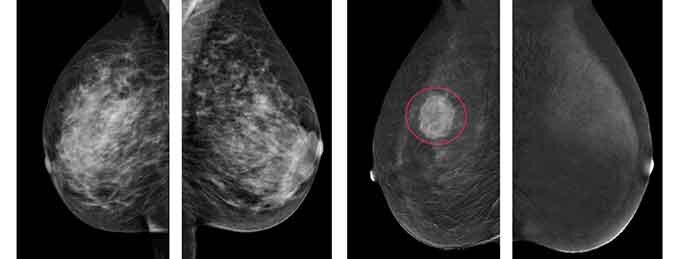

УЗИ молочных желез — диагностическая процедура, в рамках которой визуализируются состояние тканей и структура женской груди. Благодаря этому обследованию удается выявить наличие патологических процессов и возможных новообразований в том числе на начальном этапе Благодаря ультразвуковой диагностике удается выявить следующие нарушения: · воспалительные изменения · Кисты · Расширенные протоки · Абсцессы · Новообразования доброкачественные и злокачественные УЗИ молочных желёз является высокоинформативным и важным исследованием для женщин в любом возрасте. Благодаря изображению высоко качества удаётся качественно оценить состояние железистой ткани, структуру протоков, выявить новообразования малого размера и определить их особенности. Показания к проведению УЗИ В связи с высокой частотой развития заболеваний молочных желез, УЗИ груди проводится в следующих случаях: · боли и дискомфорт в любой части молочных желез; · появление нехарактерных выделений (гной, кровь и другие); · грубая кожа на

УЗИ молочных желез — диагностическая процедура, в рамках которой визуализируются состояние тканей и структура женской груди. Благодаря этому обследованию удается выявить наличие патологических процессов и возможных новообразований в том числе на начальном этапе

Благодаря ультразвуковой диагностике удается выявить следующие нарушения:

· воспалительные изменения

· Кисты

· Расширенные протоки

· Абсцессы

· Новообразования доброкачественные и злокачественные

УЗИ молочных желёз является высокоинформативным и важным исследованием для женщин в любом возрасте. Благодаря изображению высоко качества удаётся качественно оценить состояние железистой ткани, структуру протоков, выявить новообразования малого размера и определить их особенности.